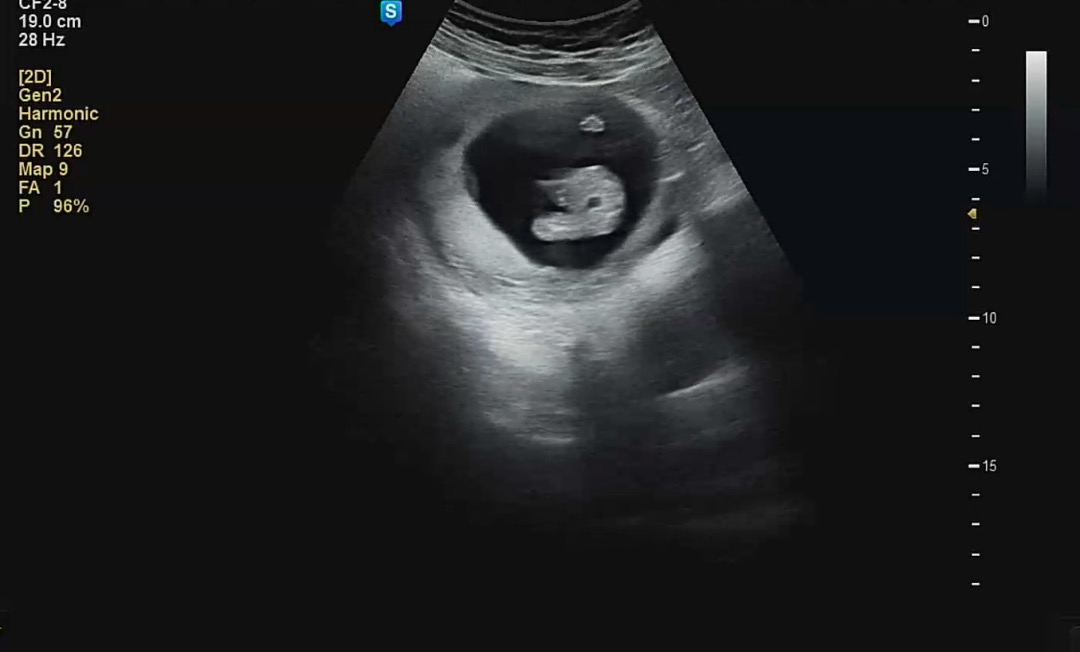

14주 초음파 아들일까요??

다리사이에 볼록한게 아들일까요?! 첫째 딸일땐 완전 매끈했거든요!!!

딸인것같아여!